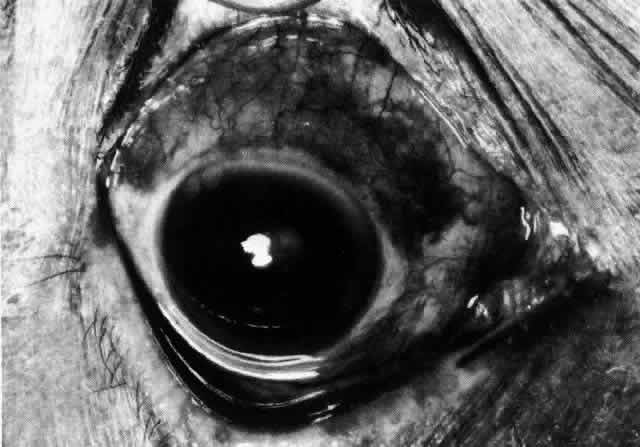

The redness of simple episcleritis may be intense, varying from a fiery-red or a brick-red discoloration to a mild red flush, but it does not have the bluish tinge that is seen in scleritis. The distribution is usually sectorial but can involve the whole anterior segment of the globe. The episcleral vessels are engorged but retain their normal radial position and architecture (Figs. 13 and 14; Color Plate 1A). In simple episcleritis, there is a diffuse edema of the episcleral tissues. These tissues are sometimes infiltrated with gray deposits that appear yellow in red-free light. Surprisingly, the eye is rarely tender to the touch.

In contrast to simple episcleritis, the infiltration and edema of nodular episcleritis are localized to one part of the globe, forming a nodule and some surrounding congestion (Color Plate 1B). The nodule can be moved over the underlying sclera, which is not edematous. The scleral plexus of vessels can be distinguished deep to the nodule, lying flat on the sclera and slightly congested but otherwise normal in color and configuration (Figs. 15 and 16). Episcleral nodules may be single or multiple but do not undergo necrosis (see Fig. 16). After multiple attacks of nodular episcleritis in the same location, the superficial lamellae of the sclera show some alteration and become slightly more transparent in this one area. TREATMENT Even without therapy, simple episcleritis improves considerably within the first week and resolves within 3 weeks (Fig. 17). Provided the eye is not too uncomfortable, most patients can be persuaded to leave the eye untreated, because the condition will resolve spontaneously. However, if it is believed that some treatment is desirable, topical corticosteroids or locally applied nonsteroidal anti-inflammatory drugs (NSAIDs) may make the eye more comfortable and speed resolution slightly (see Fig. 17).9 Use of corticosteroid drops must be continued for several days after the inflammation has subsided to prevent the exacerbation of the condition that occurs if they are stopped suddenly. Prednisolone, betamethasone, or dexamethasone drops may be administered hourly until redness disappears, and then three times daily for 4 to 5 days. Under no circumstances should topical steroids be administered continually for more than a few weeks at a time because of the very real danger of inducing steroid glaucoma and cataract. If the condition fails to respond immediately, other treatment regimens should be sought. Ocular NSAIDs can be administered four times daily until redness disappears. Glaucoma and cataract have not been observed after prolonged use, but many patients become intolerant to the use of the ointment or complain of stinging and irritation. Whereas simple episcleritis resolves rapidly without therapy, the resolution of nodular episcleritis is much slower. Local therapy is consequently of much more value; the same regimen of treatment is followed. In the few patients in whom episcleritis becomes indolent, or in whom recurrences are so numerous that the patient becomes incapacitated, it is reasonable to consider systemic therapy with NSAIDs such as flurbiprofen (Froben), 100 mg three times daily, which usually gives immediate and prolonged relief of symptoms and signs. It is important to note that not all of the NSAIDs work in this condition. Treatment may be terminated abruptly when the condition comes under control. The complications of episcleritis are minor and are not responsible for any decrease in visual acuity. COURSE AND PROGNOSIS Whether treated or not, simple episcleritis will resolve in 10 to 21 days. It will usually reappear at irregular intervals and then eventually disappear. An accurate 12-month record kept by a patient who went without treatment is shown in Figure 18. He was free from any further attacks for 3 years. He then had four attacks in the next 3 months and has had none since. No etiologic or precipitating factor has been found. In nodular episcleritis, the nodule initially increases rapidly in size, sometimes reaching the size of a split pea. Thereafter it gradually regresses over a variable period and eventually disappears, although this may take up to 2 months without treatment. Recurrences occur also in nodular episcleritis, but the two varieties are not mutually exclusive (a simple episcleritis may recur as a nodular episcleritis and vice versa). However, episcleritis never develops into scleritis in the same attack, although it invariably accompanies scleritis. Of 180 patients initially diagnosed as having episcleritis, only 4 developed scleral involvement.10 Episcleritis is an entirely benign condition, although it may be a great nuisance to the patient. It may recur over a period of many years, but it rarely leaves any residual ocular changes except for some areas of scleral transparency or localized stromal keratitis in those patients who have had severe attacks of nodular disease occurring always at the same site. Of 180 patients analyzed,10 only 2% had a decrease in visual acuity of two lines or more within a year of the onset, and in every case this was from increasing involutional cataract. |